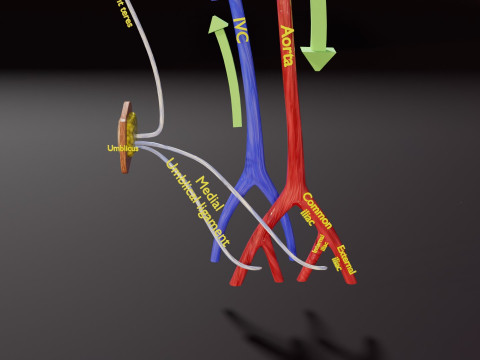

The model meshes include adult circulation versus circulation in Tetralogy of Fallot (TAF), arrow labels and text labels. The blood flow in a patient with Tetralogy of Fallot is outlined in this model. To contrast it to normal blood circulation a separate model of normal circulation is included. The Tetralogy of Fallot (OVER RIDING OF AORTA, PUL STENOSIS, VENTRICULAR SEPTAL DEFECT, RIGHT VENTRICULAR HYPERTROPHY), fossa, ligament teres , venosus, and arteriosus are duly depicted with proper labelling and blood flow directional arrows. Excellent model for teaching, demonstration and knowlegde of human body. The models include both procedural and image textures blend files separately. The texture file include diffuse, roughness and normal png and jpeg based on non overlapping UV maps.